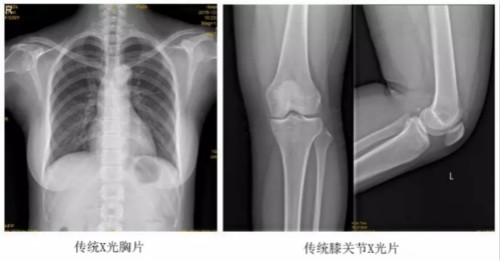

以某院所摄X光片为例,对比传统摄片与全身拼接功能的区别:

传统X光片只能观察每个部位的局部情况,无法在统一体上进行连续、全面的观察,全脊柱及下肢全长片则能直观的看到整体形变。通过DR全身拼接功能实现的完整成像,为诊治脊柱及下肢畸形提供了完美的临床影像依据,对临床诊断、术前手术方案的制定和术后疗效的评估等临床应用具有十分重要的意义,有效满足了此类疾病临床诊断和治疗的要求。